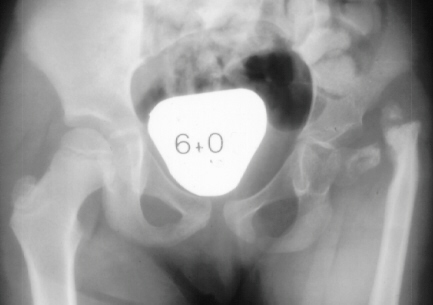

an acetabulum is seen on x-ray, the femoral head will also be

present although ossification may be severely delayed.